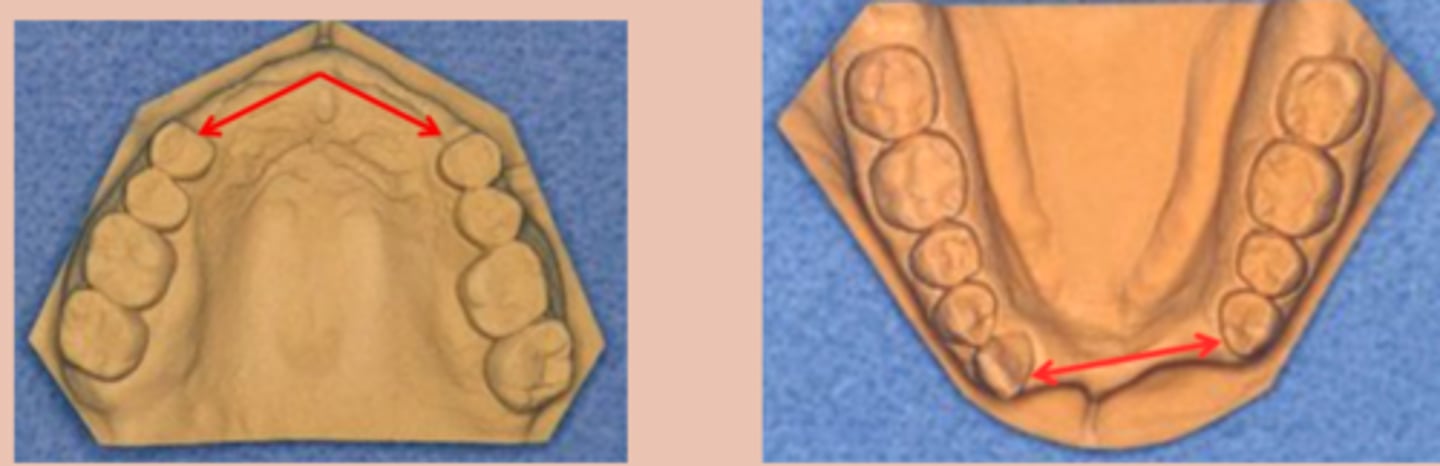

Rules 6, 7, and 8

pertain to modification spaces, which are designated with Arabic numerals. Allows further description of clinical situation, since many patients have more than one edentulous area that do not fit the Kennedy class I scenario

modification space (rule 6)

Each additional edentulous area (beyond those that determine classification) is a _______ - not each additional missing tooth (Rule 7).

Class II Mod 2

which Kennedy Class?

Class I Mod 1

which Kennedy Class?

Class III Mod 3

which Kennedy Class?

Class III Mod 1 (Class I Mod 2 if replacing 2nd molars)

which Kennedy Class?

Class III mod 5

which Kennedy Class?

Class III Mod 2

which Kennedy Class?